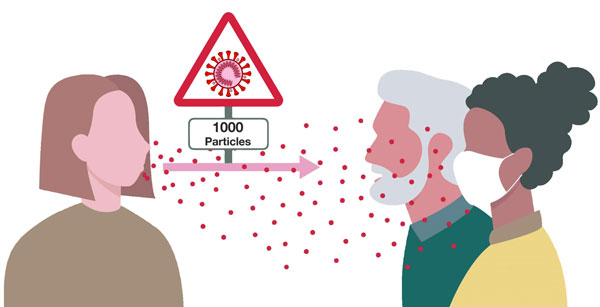

- محصولات کرونا